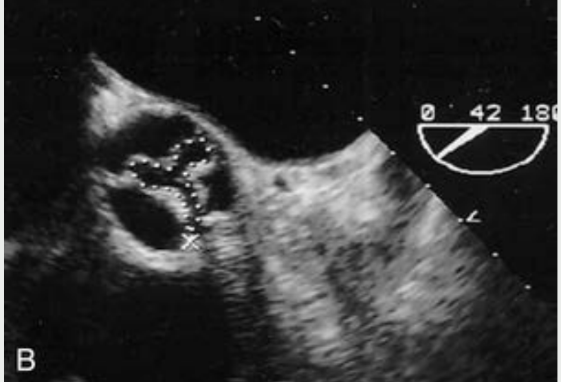

ā¢Planimetry of aortic valve anatomic area

(cm2)

⢠Anatomic (geometric) CSA of the aortic valve orifice as

measured by 2D or

3D echo

Planimetry is difficult in

stenosis due to? Planimetry can used during what

stenosis due to

calcification around the

valve with TTE

Planimetry can used

during TEE